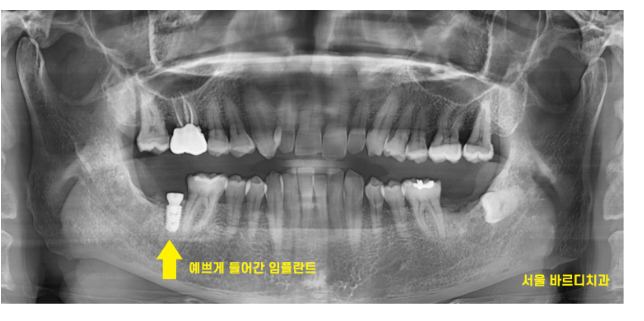

하남시청치과 처음 방문해주셨을 때

왼쪽, 오른쪽 맨 아래 끝에 어금니가

각각 1개씩 상실한 채로 오셨습니다.

하남시청치과 임플란트 그 결과는,,?

231229

원하는 위치에 각도가 예술로 정확히 들어갔습니다.